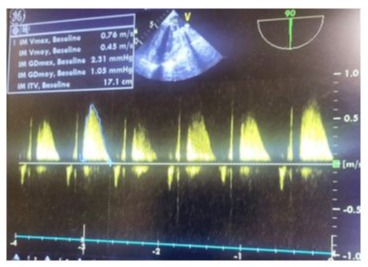

64-year-old female, with medical history of hypertension, hyperlipidemia, symptomatic mitral insufficiency presented initially with a history of repetitive episodes of acute cardiac insufficiency, worsening dyspnea on exertion, orthopnea, paroxysmal nocturnal dyspnea. Despite optimization of medical therapy with sacubitril/valsartan, spironolactone, dapagliflozin, high-dose furosemide, bisoprolol, her symptoms continued to deteriorate. In her hospitalization in cardiology, the physical examination revealed signs of congestive heart failure, including elevated jugular venous pressure, bibasilar crackles, and a pansystolic murmur loudest at the apex radiating to the axilla. Transthoracic Echocardiography (TTE): Showed severe mitral regurgitation with a flail posterior leaflet, left ventricular dysfunction with an ejection fraction of 50%, tele-systolic diameter at 44mm, dilated left atrium and ventricle, and pulmonary hypertension with an estimated systolic pulmonary artery pressure of 60 mmHg. Transesophageal Echocardiography (TEE) has confirmed TTE findings and provided detailed assessment of the mitral valve pathology, including the mechanism and severity of regurgitation, as well as assessment of the tricuspid valve and right ventricular function. Given the severity of her symptoms and the progressive nature of her disease despite optimal medical therapy, she was scheduled for surgical intervention 3 months later after stabilization and complete decongestion with the addition of higher doses of furosemide. The plan involved mechanical mitral valve replacement given that mitral valve repair was deemed unfeasible based on the TEE data and the surgical team's experience and tricuspid annuloplasty to address the valvular pathology and alleviate symptoms of heart failure. The patient underwent cardiac surgery via median sternotomy with cardiopulmonary bypass. Mechanical mitral valve replacement (size 29) and tricuspid annuloplasty using a 32-mm semi-rigid annuloplasty ring were performed. TEE provided detailed intraoperative assessment of the mitral and tricuspid valves, confirming the severity of regurgitation (Figure 1) (video 1), mechanism of valvular dysfunction, and the need for surgical intervention. It also allowed for real-time monitoring of cardiac function and assessment of the adequacy of the surgical repair (Figure 2,3) showing a reduction in sub aortic velocity-time integrals (VTI), indicative of left ventricular dysfunction and pulmonary hypertension through the analysis of the pulmonary regurgitation velocity. With a cross-clamp time of 60 minutes and a cardiopulmonary bypass (CPB) duration of 120 minutes however, the weaning from cardiopulmonary bypass was complex, requiring central extracorporeal membrane oxygenation (ECMO) support. Progressive doses of inotropic support including epinephrine Corotrope, norephedrine, and inhaled nitric oxide were administered due to persistent hemodynamic instability with evident signs of pulmonary hypertension including a hypokinetic and dilated right ventricle, paradoxical septum, significant pulmonary regurgitation with elevated mean pulmonary artery pressure (MPAP), systolic pulmonary artery pressure (SPAP), and diastolic pulmonary artery pressure (DPAP), despite high doses of inotropes and pulmonary vasodilators. The left ventricular function was clearly impaired with a hypokinetic left ventricle, which dilated after a few minutes of complete cessation of cardiopulmonary bypass support. Due to the inability to wean off cardiopulmonary bypass (CPB), And after verification via intraoperative transesophageal echocardiography (TEE) of the proper functioning of the mechanical valve (video 2,3,4), central ECMO was implemented with arterial cannulation at the left ventricular apex and venous atrial cannulation, aiming for bridge to recovery and to prevent recurrent pulmonary edema episodes on peripheral ECMO, given the high filling pressures estimated by deceleration time and the E/Vp ratio and the falling ETT has shown an absence of holosystolic aortic valve opening under veno-arterial ECMO after failure to wean from cardiopulmonary bypass, indicating severe ventricular dysfunction and the non-contribution of the heart to the cardiac output generated by mechanical circulatory support associated to proper function of the Saint-Jude-Medical bileaflet valve with a low mean transvalvular gradient, indicative of postoperative left ventricular dysfunction. (Figure 4,5)Unfortunately, the patient developed significant bleeding, the advanced laboratory tests, which took time to arrive because we do not have localized laboratory devices to guide initial therapeutic strategies, a massive transfusion of platelets, fresh frozen plasma, packed red blood cells and fibrinogen concentrates has been performed, prothrombin complex concentrates were not available. Given the hemostatic disorders with laboratory evidence of hypofibrinogenemia and thrombocytopenia, suggestive of coagulopathy and consumptive coagulopathy secondary to surgical trauma and cardiopulmonary bypass, and the need for a reoperation was not taken, the ECMO pump flow continued to decline despite increasing, due to venous line collapse following a decrease in volume (video 5,6). Despite aggressive resuscitative efforts, she succumbed to complications and expired 24 hours after surgery.

Figure 2: Pre-cardiopulmonary bypass (CPB) intraoperative TEE showing a reduction in subaortic velocity-time integrals (VTI), indicative of left ventricular dysfunction.